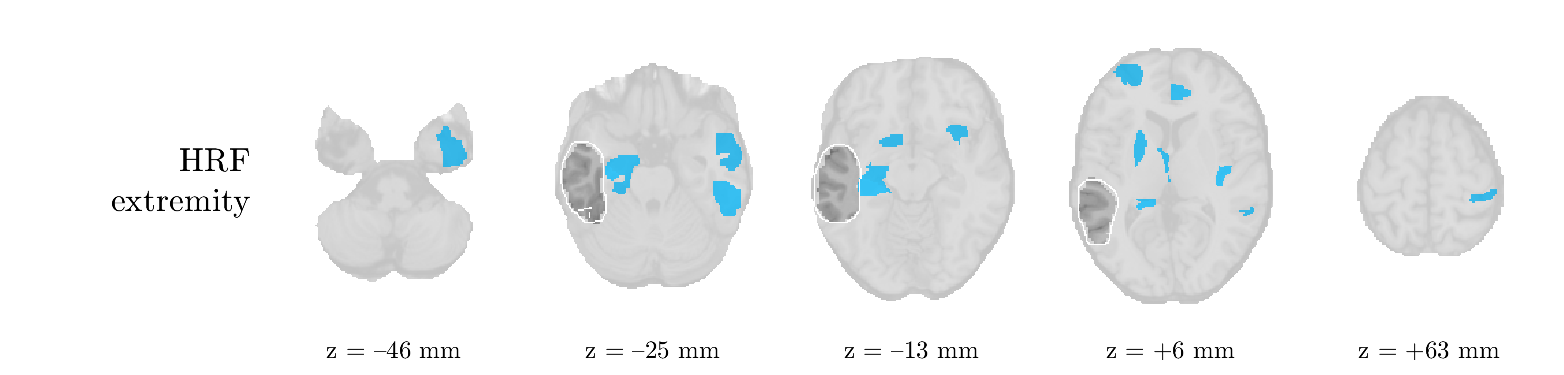

Patient 2

We analyze the solution with sources, and show the results in Figure 3 and 4. As for patient 1, we found a source which is strongly correlated to the MWF envelope, and which had a mostly low-frequency behavior characteristic for spikes. The topography is mostly uninformative, and does not clearly correspond to the patient’s clinical data. The third source is mostly present at both sides of the head, is very sparsely active in time, and has a high-frequency content: this is most likely an artifact due to the neck muscles. Again, there is one of the highest-entropy HRFs which belongs to a ROI in the IOZ. Now, the waveform is clearly resolved from the other HRFs, through the strong initial dip (before 0 seconds). Such a dip is sometimes observed in HRFs, but its underlying physiological mechanism is not yet fully understood. It is possible that this dip reflects altered vascular autoregulation near the IOZ (cfr. the explanation in the Section 1 of the main text), or a rapid depletion in oxygen due to IED generation (before the IED becomes visible on the EEG). Figure 4 furthermore shows that the IED-related component is significantly active in parts of the IOZ, and deactive in others. As mentioned earlier, this deactivation may or may not be due to errors in sign correction. Interestingly, the ROI with the high alteration in neurovascular coupling is distinct from both the activated and deactivated ROIs.